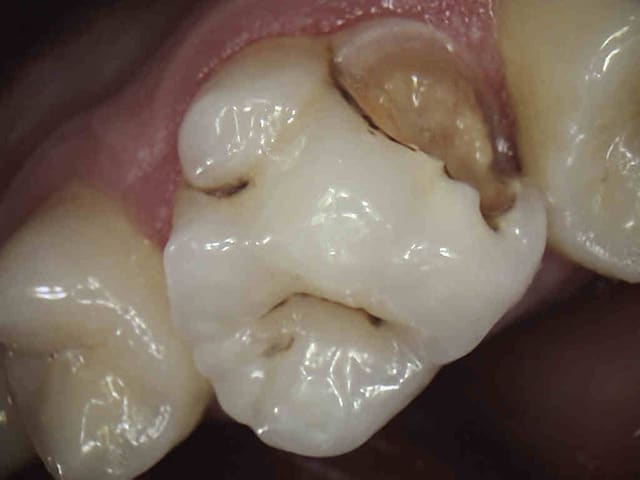

Allez, celui là je le trouve assez satisfaisant, vite plié:

1h pour refaire les compos, 1h15 rtr+rcr+prep+pro+emp, 30min pour poser. Couronne partielle, collage multilink.

(bon, après la photo, j'ai meulé un peu l'angle distal hein)